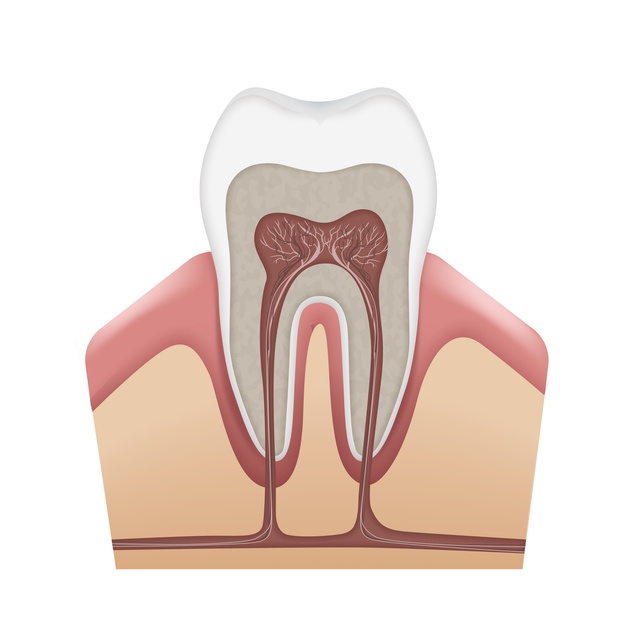

■ Quick Answer Yes — but only if it contains fluoride or nano-hydroxyapatite. Many products labelled “remineralising” contain neither and have limited clinical evidence. Here’s how to tell the difference. Not all toothpastes that claim to remineralise actually do — the ingredient list tells the real story. What Does “Remineralising” Actually Mean? Enamel is the …